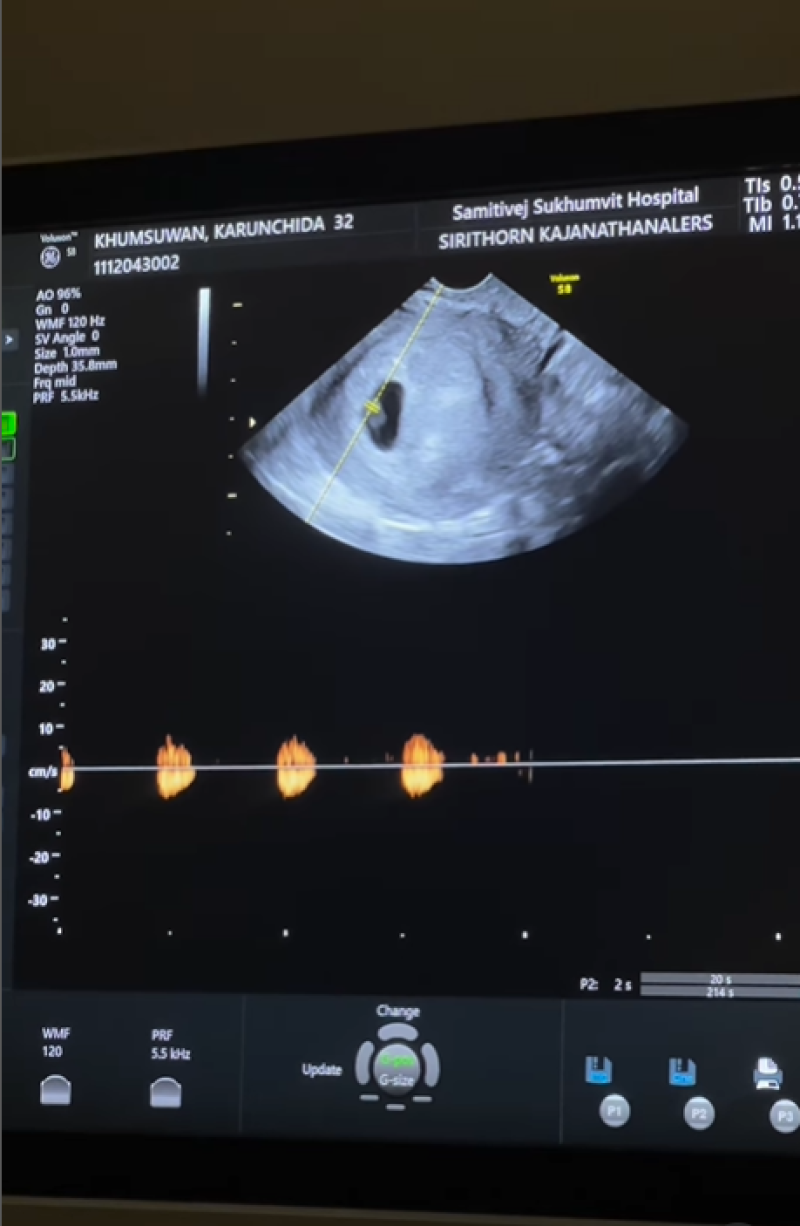

เรียกได้ว่า เป็นอีกหนึ่งคู่ที่ชอบเผยโมเมนต์น่ารักๆและตลก ออกมาให้แฟนๆได้ดูอยู่บ่อยๆ อย่าง ดาราสาว พราวฟ้า การัญชิดา กับสามี เสี่ยโบ๊ท ณัฐเดช ที่ล่าสุด ทั้งคู่ออกมาประกาศข่าวดีแล้วหลังแต่งงานมาได้สักพัก โดยได้เผยคลิปลงอินสตาแกรม พร้อมระบแคปชั่นว่า 09.02.2024 #9weekspregnant เบบี๋มาแล้วค่า เสี่ยโบ๊ทไม่ทำให้ผิดหวัง ของเค้าดีจริงๆ #prawfarboat1109 @yindeeman

ภาพจาก prawfar_kk